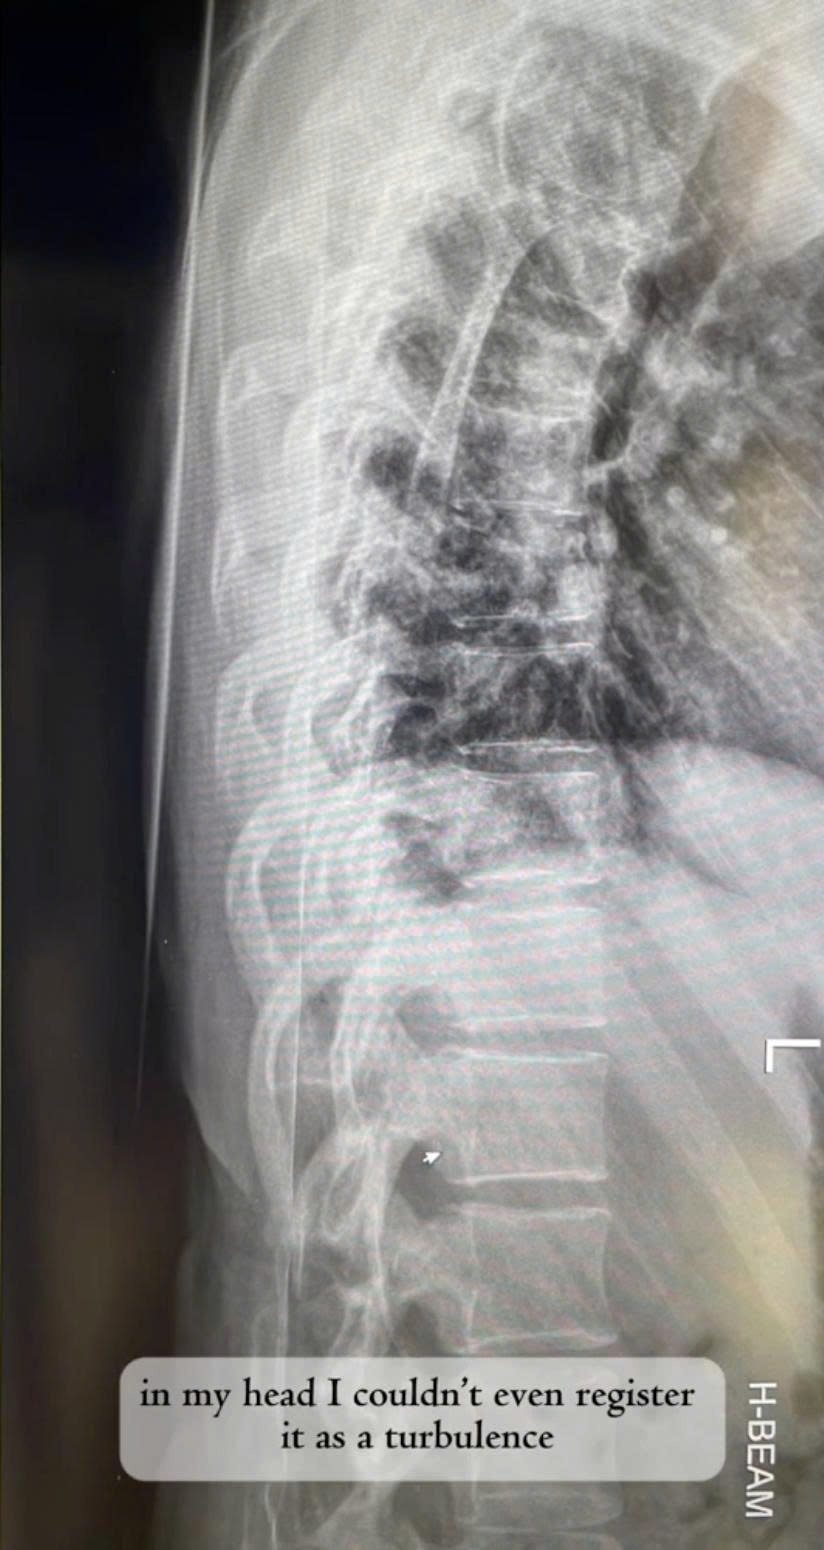

Khi xảy ra tai nạn, Mia đang ở trong buồng vệ sinh và bị gãy xương sống do va đập. Cô chứng minh câu chuyện của mình bằng ảnh chụp X-quang cột sống cũng như hình ảnh cô nằm trong bệnh viện.

"Trong đầu tôi thậm chí không nhận ra đó là nhiễu động, tôi cứ nghĩ máy bay thực sự đang rơi xuống", Mia nhớ lại.